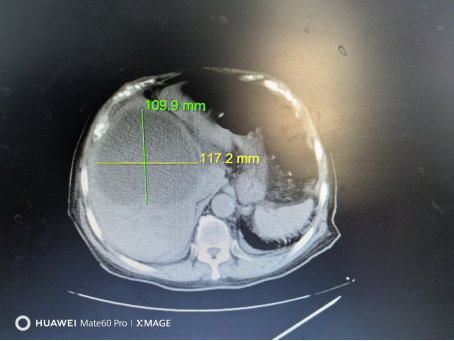

术中引流出800ml黄色腥臭味脓液,整个过程病人清醒,无任何不适。术后患者体温保持正常,未出现发热。术后1周复查CT显示:脓腔内脓液抽取干净,脓腔塌陷。患者现已治愈出院,身体状态良好。